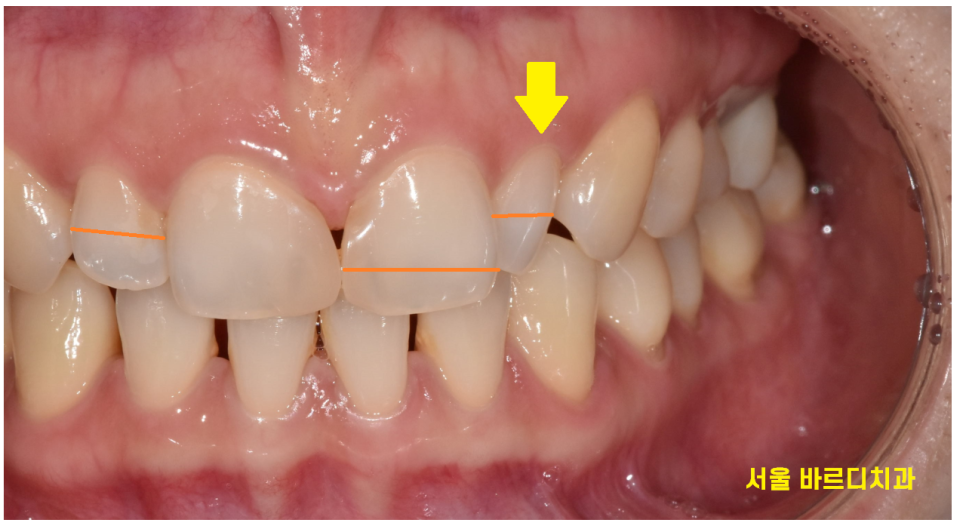

환자분은 바로 옆 대문니가 크다 보니

치아가 각도상 비틀어져 있어서

유독 작게 보이네요.

반대편 같은 치아의 경우 각도는 제대로 되었지만

이 역시 왜소치에 속합니다.

왜소치 라미네이트 제작을 위해

치아를 삭제한 사진입니다.

아래 치아는 건들이지 않은 자연치

윗니의 경우 치아를 삭제했는데

두께가 크게 달라지지 않은 것을 보실 수 있을겁니다.

(최소한만 삭제하여 치아를 아껴줍니다!!)